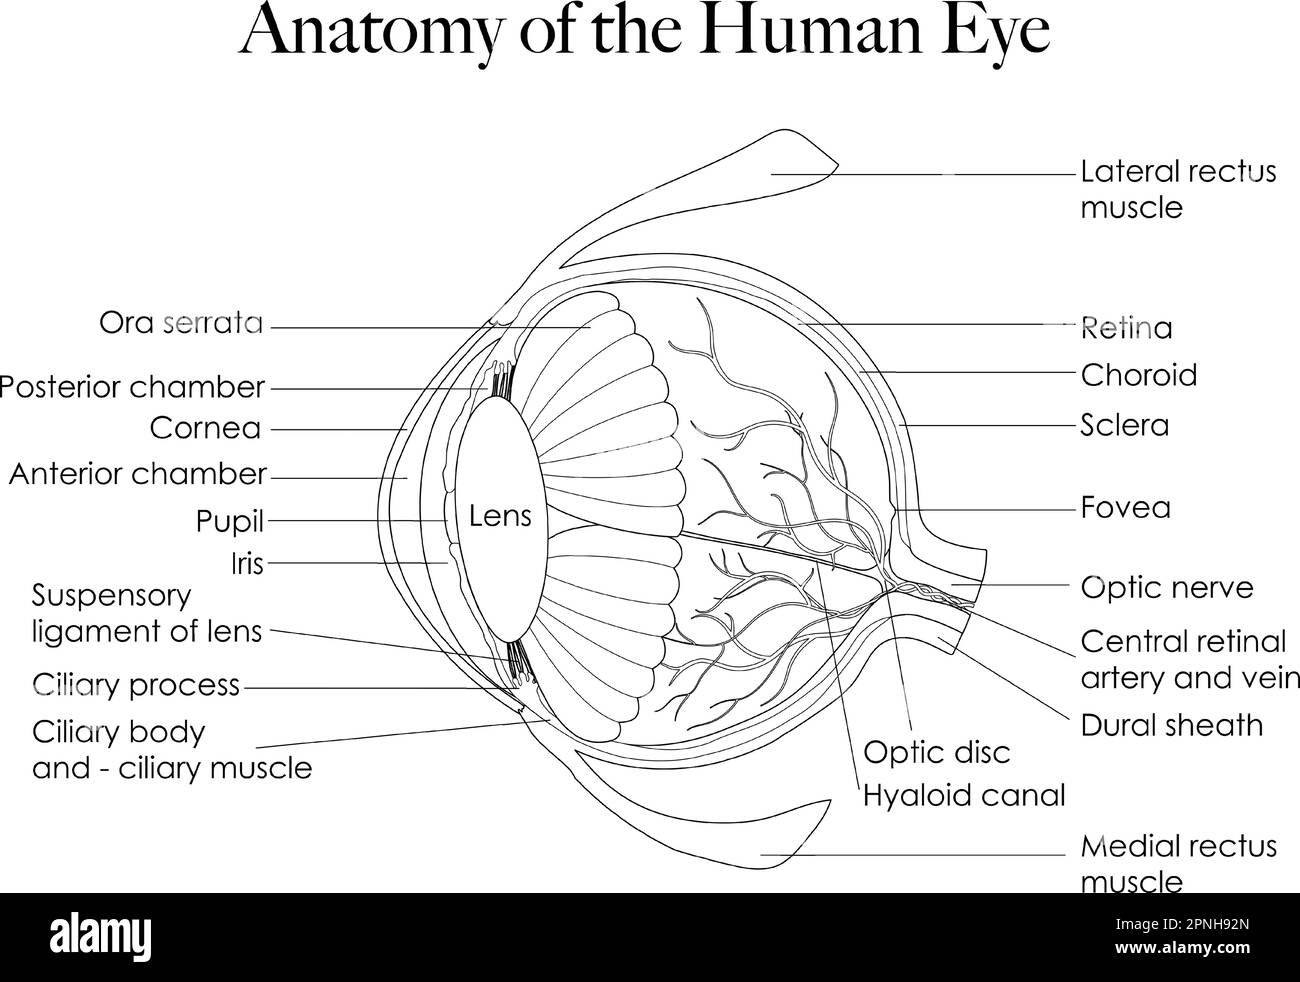

RF2PNH92N–La grafica in bianco e nero può essere utilizzata come pagina da colorare. Presenta l'anatomia dell'occhio umano, consentendovi di esplorare la sua complessa struttura.